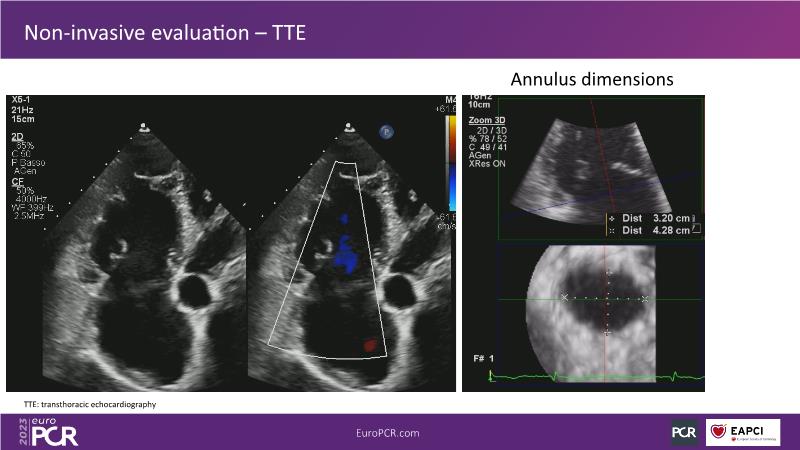

Tailoring tricuspid regurgitation patient treatment with the PASCAL Precision system

- To discuss the different tricuspid regurgitation phenotypes that can be treated with the PASCAL Precision repair system

- To participate in a case-based discussion using the PASCAL Precision repair system for the treatment of tricuspid regurgitation